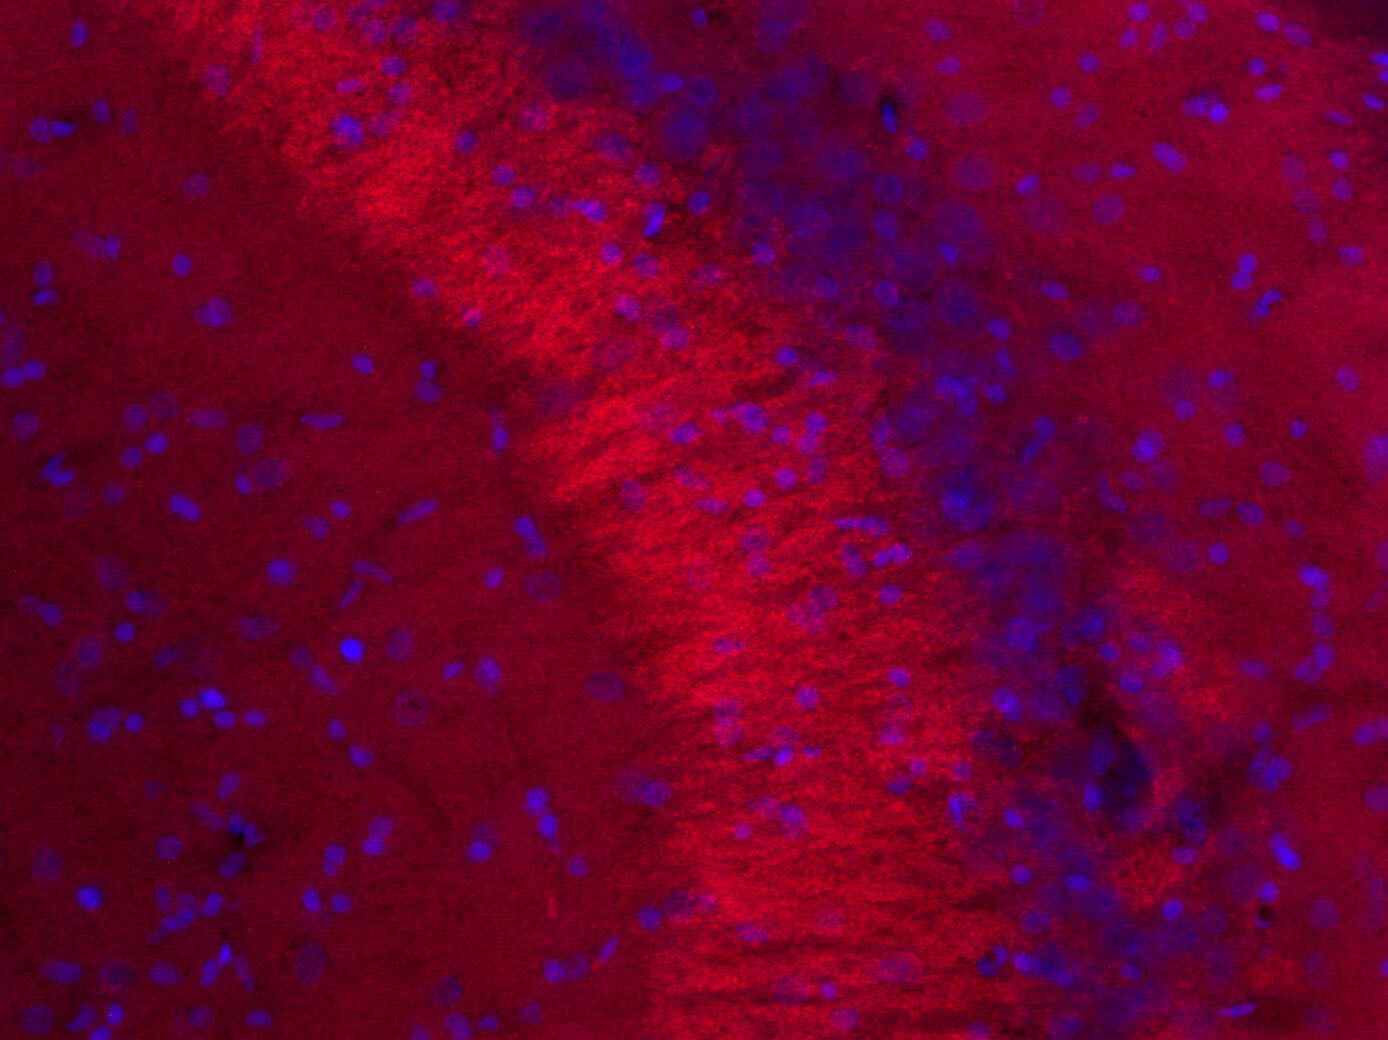

CD279 (PD-1) Monoclonal Antibody (eBioJ105 (J105)), PE (12

CD279 (PD-1) Monoclonal Antibody (eBioJ105 (J105)), PE (12